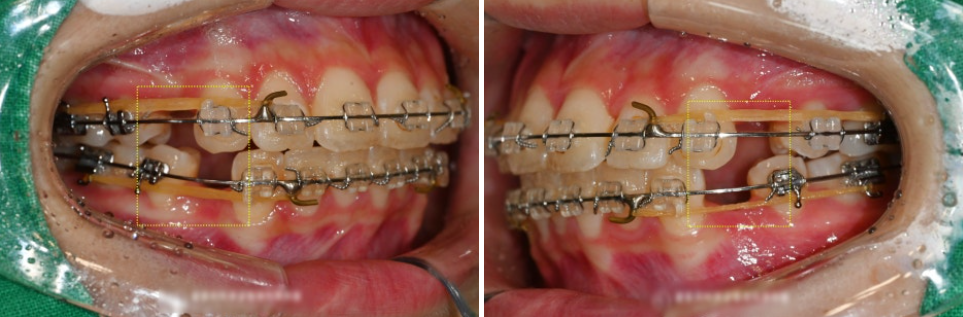

『초진』

아래 사진들은 면목동 치과 에서

직접 촬영한 구강 내 사진들입니다.

상기 사진에서 이 환자가

치열의 불규칙성을 갖고

있다는 것을 보여줍니다.

총생과 더불어서 Rotation 이

되어 있다는 점도 눈에 띕니다.

Overjet, Overbite 의 양 또한

일률적이지 않다는 것을 보여줍니다.

이는 비심미적인 요소를 드러내는

대표적인 예가 될 수 있습니다.

입 천장(구개면)에 악궁 확장 장치를

부착한 것을 볼 수 있습니다.

가운데에 있는 스크류 홀을 활용하여

스크류를 돌리면 양 옆으로 밀어내는

힘이 발생이 되면서 악궁이 벌어집니다.

깜빡거리는 위치를 보면,

악궁이 벌어짐에 따라서

큰 앞니들 사이에 공간 또한

조금씩 만들어진 것을 볼 수 있습니다.

중간 f.u 사진입니다.

시간의 흐름에 따라 배열도 점점 정렬되고

있는 모습을 볼 수 있습니다.

브라켓을 떼기 전 3개월 전으로는

텅 비었던 공간에도 폐쇄가 잘 이루어져

이제는 빈 곳 없이 잘 메꾸어져 있는 모습을

바로 볼 수 있었습니다.

처음 오셨을 때만 하더라도

틀어진 앞니로 인해

V자 나비 치아 형태가 눈에 띄었지만,

완료된 모습에서는 가지런하게 위치해있는

전치부 배열을 확인할 수 있었습니다.